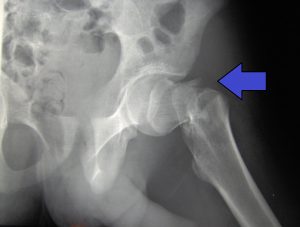

En el último vídeo del canal de ArtroEsport en YouTube, el Doctor Antoni Fraguas te explica una nueva técnica de femoroplastia para reforzar la osteoporosis femoral y evitar su fractura.

En el último episodio de Artro Esport Podcast, el Dr. Fraguas explica las innovaciones que previenen la fractura de fémur. Lo hace en este capítulo en formato entrevista. Asimismo, el

Existe una revolucionaria innovación que previene las fracturas de fémur en ancianos. Los que ya somos mayores hemos escuchado de nuestros abuelos que romperse el fémur a principios del siglo

Los que ya somos mayores hemos escuchado de nuestros abuelos que romperse el fémur a principios del siglo pasado era casi la condena de una muerte escalofriante. Imaginaos: en la